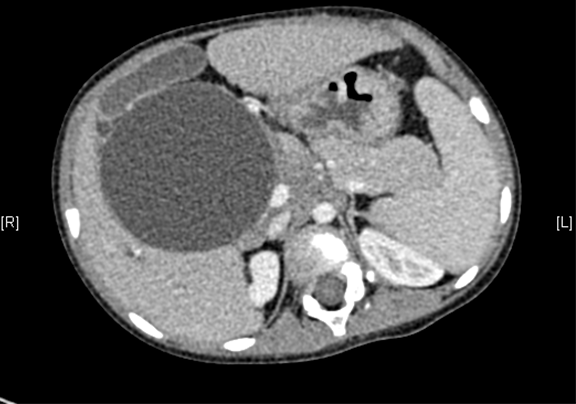

上腹部增强CT:考虑先天性胆管扩张症(胆总管明显)。

术前CT检查:

动脉期

静脉期

平衡期